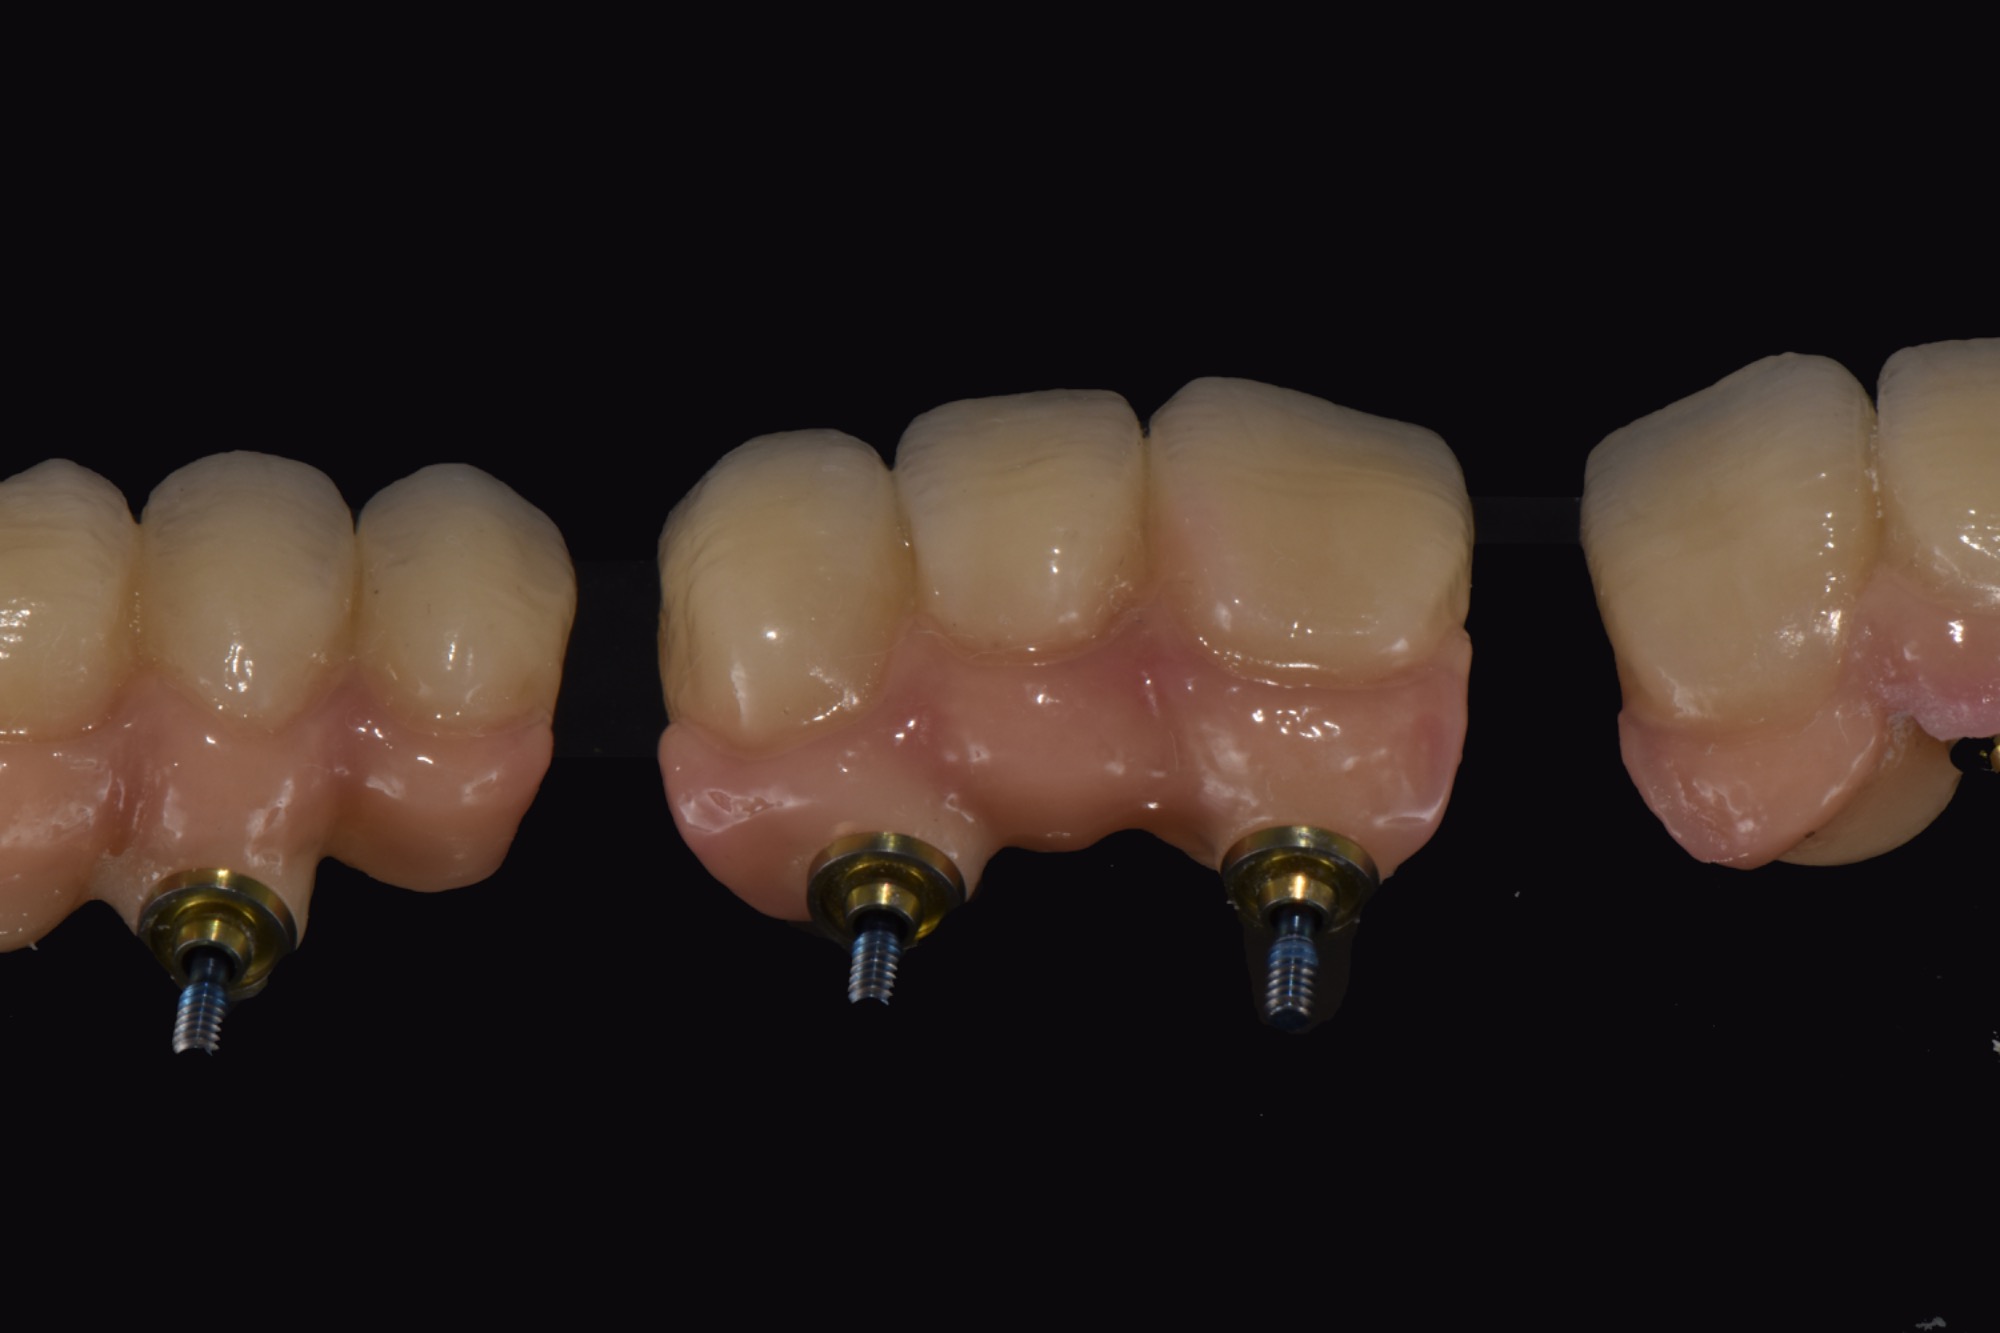

Implantatbrücke zur Wiederherstellung der Zahn- und Zahnfleischanteile mit verschraubten Brücken.